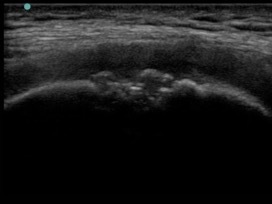

Knee Anterior Trochlear Osteochondral Defect Medial Longitudinal Image